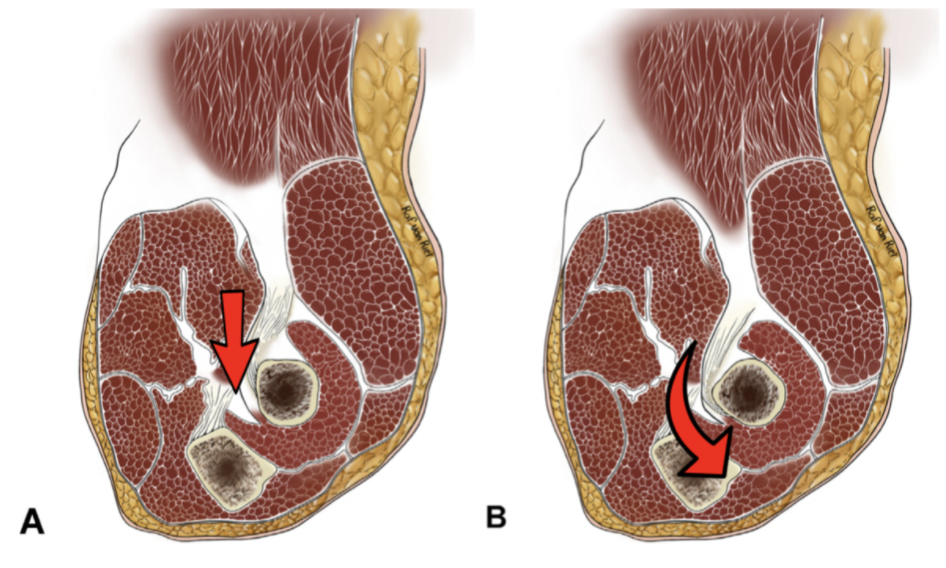

Tommy John Injury: Journey Back to Throwing after a UCL Injury

Anatomy of Ulnar Collateral Ligament (UCL) Originating on the anteroinferior surface of the medial epicondyle of the humerus and inserting onto the sublime tubercle of ...